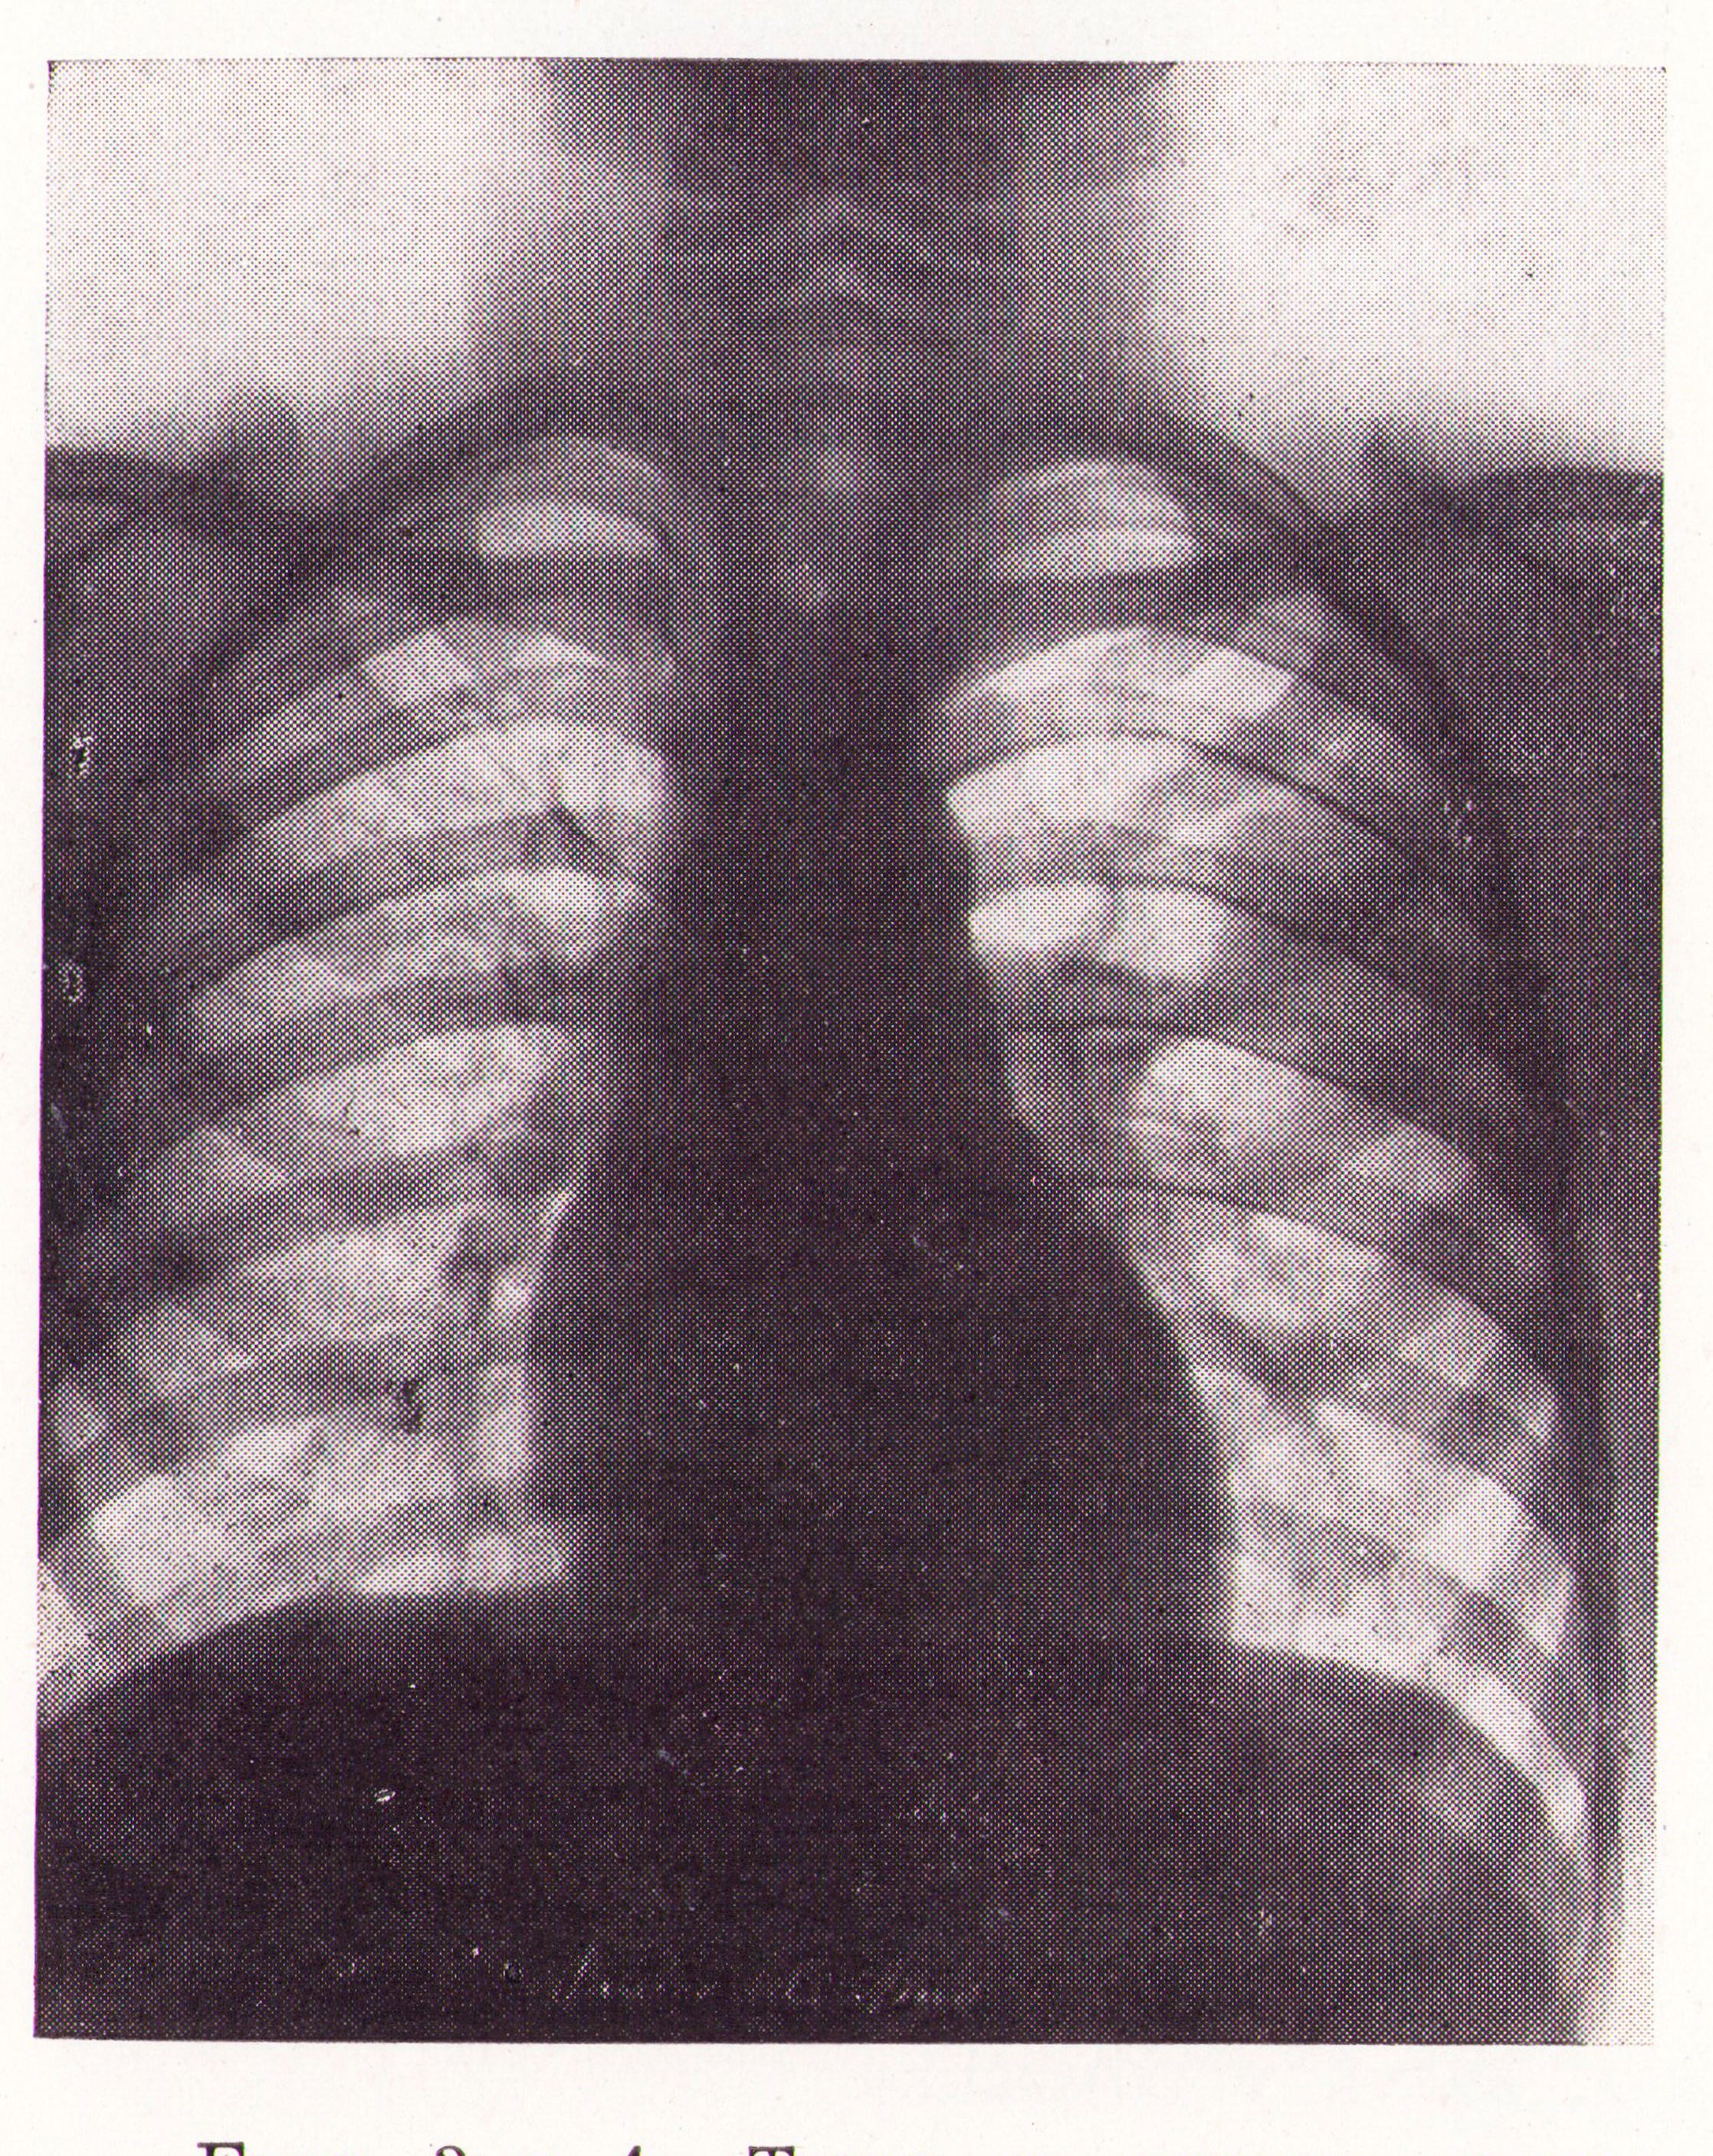

Quistes evacuado por vómica inapercepta

Fig.3. Revista Española de ciencias médicas, Clínica y laboratorio, 1953.